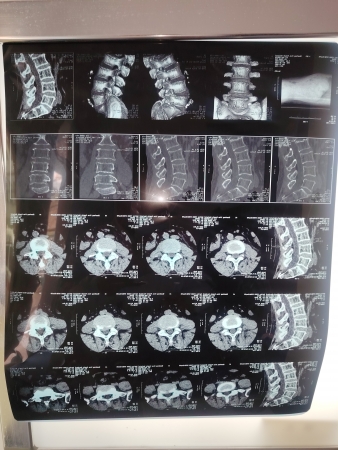

中村镇刘XX是**家属,由于积劳成疾到县级医院诊断为腰椎L4-5突出,股骨头坏死,膝关节退行性病变。经过治疗腰部没有不适,原来双侧股骨头部位疼痛不适,现在没有不适感局部也没有压痛,拍X线片显示:股骨头部略变窄毛糙;就是膝关节走路时有点不适,建议到上级医院做核磁共振检查明确诊断。